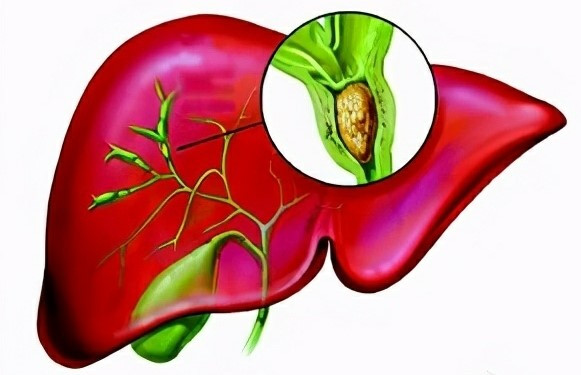

双重作用!上海大学等单位合作发文:胰腺癌治疗潜在靶点